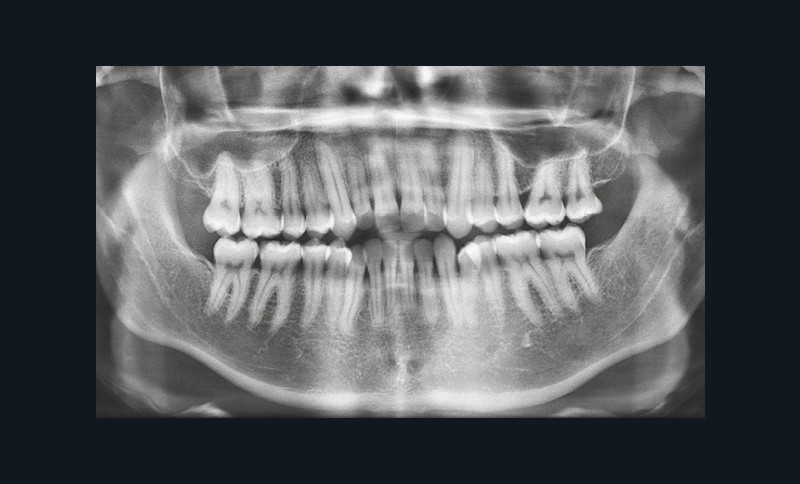

L’orthopantomogramme révèle l’absence des troisièmes molaires et la présence d’espaces rétro-molaires mandibulaires (fig. 9). Les analyses céphalométriques (fig. 10) mettent en évidence une classe I squelettique (ANB = 2°) sur un schéma facial hyperdivergent (FMA = 29°).